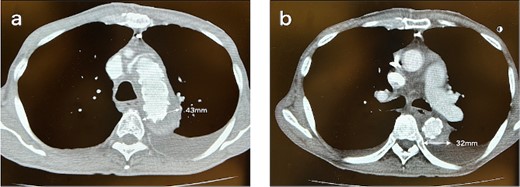

A 62-year-old male presented at the previous hospital with left hemiplegia. Computed tomography (CT) detected an aortic dissection with malperfusion of the right brachiocephalic artery, necessitating a referral to our institution. Preoperative CT showed the primary entry tear in the distal aortic arch and a patent false lumen. A total arch replacement was successfully performed using the fenestrated FET technique. The surgical procedure involved median sternotomy, establishment of extracorporeal circulation with right atrial drainage and perfusion via right axillary artery, circulatory arrest at 28°C and selective cerebral perfusion to perfuse all cervical vessels. Myocardial protection was provided by retrograde cardioplegia. Following resection of the aorta at zone 1, FET was inserted and deployed into the aorta, perfusing blood from the femoral artery. Fenestration of the graft at the ostium of the second and third cervical branches was performed. A U-shaped graft was placed around cervical branches, and three 4-0 polypropylene U-shaped sutures were roughly placed to fix the open stent graft, leaving some gaps between the sutures. Subsequent procedures included anastomosis of a four-branch graft to the distal aorta, reconstruction of the brachiocephalic artery and proximal anastomosis. Postoperative contrast-enhanced CT on day 5 showed no endoleak and favorable remodeling of the descending aorta (Fig. 1). However, after 6 months, follow-up CT detected a fenestration-related endoleak and an enlarged aortic arch (Fig. 2), prompting reoperation. The reoperation involved median re-sternotomy, establishment of extracorporeal circulation with right femoral vein drainage and perfusion via an 8-mm graft anastomosed to the left axillary artery, circulatory arrest at 28°C, and selective cerebral perfusion to perfuse all cervical vessels. Upon opening the artificial graft, it was observed that the stent graft had some gap between fixed U-sutures and had become detached from the aorta, revealing a small entry adjacent to it, which communicated with the false lumen. The left subclavian artery (LSCA) was ligated, and the left common carotid artery was transected at its origin and sutured. An open stent was inserted distally, followed by placement of a felt strip and a 4-0 running suture. Subsequent procedures included anastomosis of a four-branch graft to the distal aorta, reconstruction of the three cervical branches and proximal anastomosis. The surgery was completed without complications. Postoperative contrast-enhanced CT on day 5 revealed resolution of the endoleak with no blood flow into the false lumen of the arch. Follow-up CT 3 months after discharge revealed favorable remodeling of the aortic arch (Fig. 3).

CT 3 months after redo surgery reveals no endoleak and no flow in the false lumen, and remodeling of the aorta at the levels of the aortic arch (a) and the carina of the trachea (b). Sagittal image (c). An illustrative diagram (d) shows the postoperative schema.